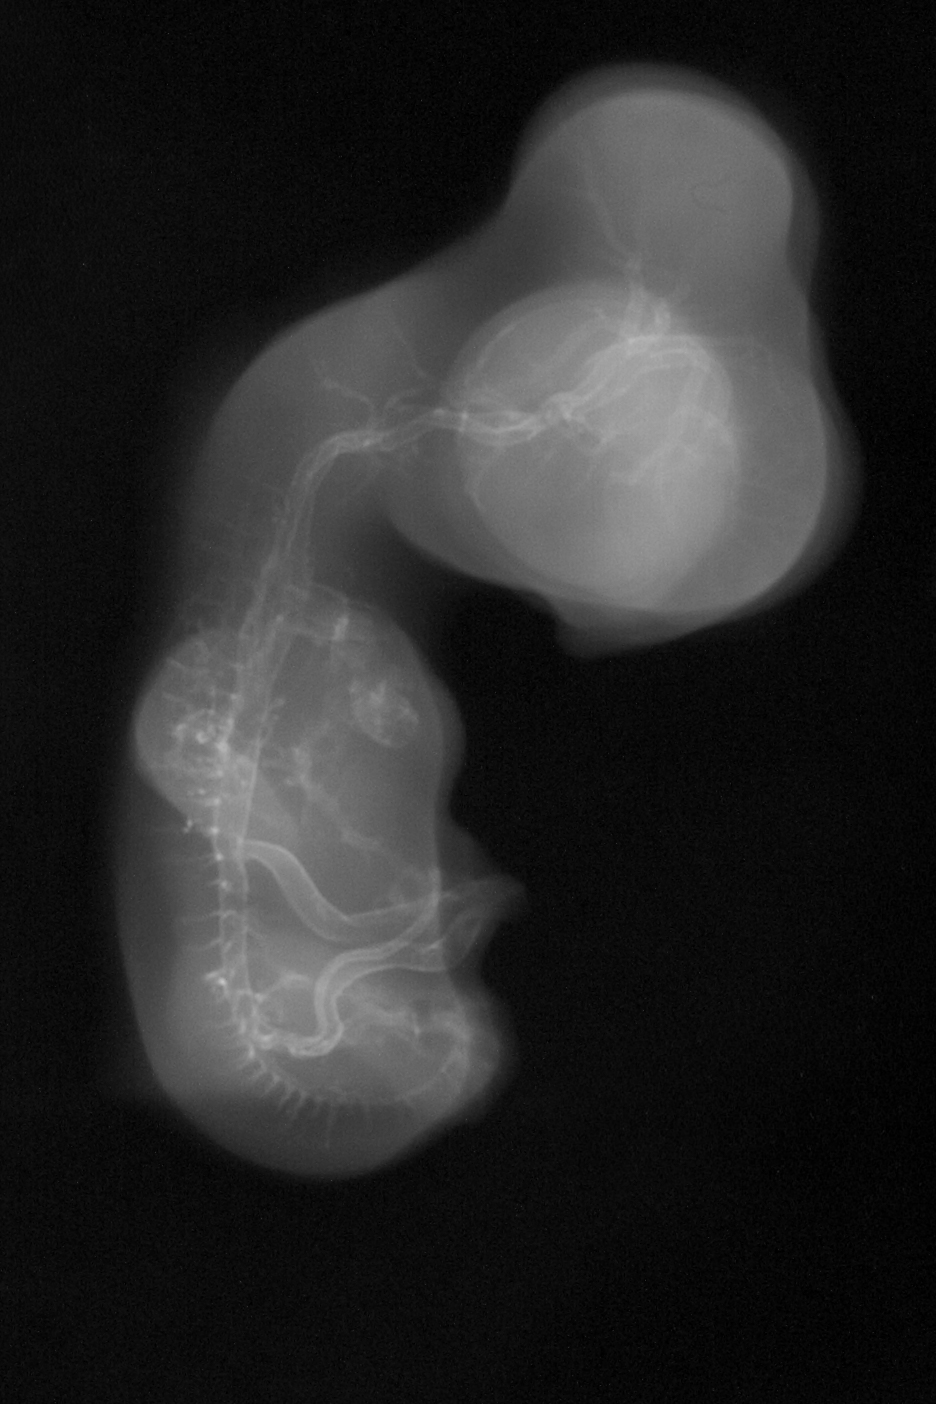

X-Ray Micrographs